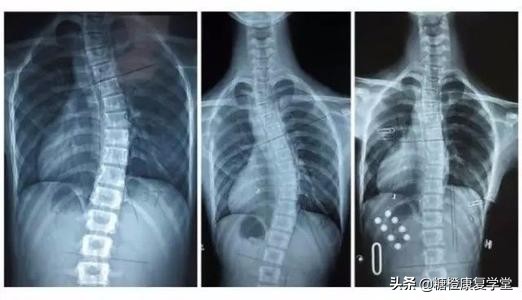

ADS是由于非对称性脊柱小关节及椎间盘退变,合并骨质疏松及压缩性骨折等造成的脊柱冠状面失衡,临床定义为骨骼发育成熟的人群中,出现Cobb角>10°的脊柱畸形。

2.脊柱侧弯:高低肩、或肩胛骨不对称